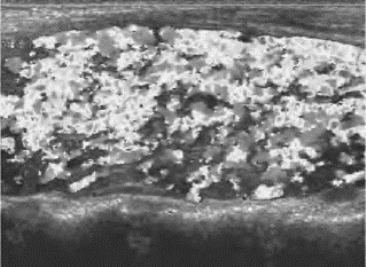

甲状腺对称性、均匀性肿大,包膜平滑。回声受病程和治疗的影响,内部呈中低回声区,分布均匀,有时欠均匀,一般无结节。CDFI:甲状腺内血流十分丰富,呈现“火海征”(图7-5)。STA、ITA内径增宽,PWD显示流速增快、流量增多,阻力减低。结节性甲状腺肿继发甲状腺功能亢进(以下简称甲亢)时,可显示出结节性甲状腺肿的超声表现。

图7-5 甲亢的彩色血流“火海征”超声图(见彩图5)